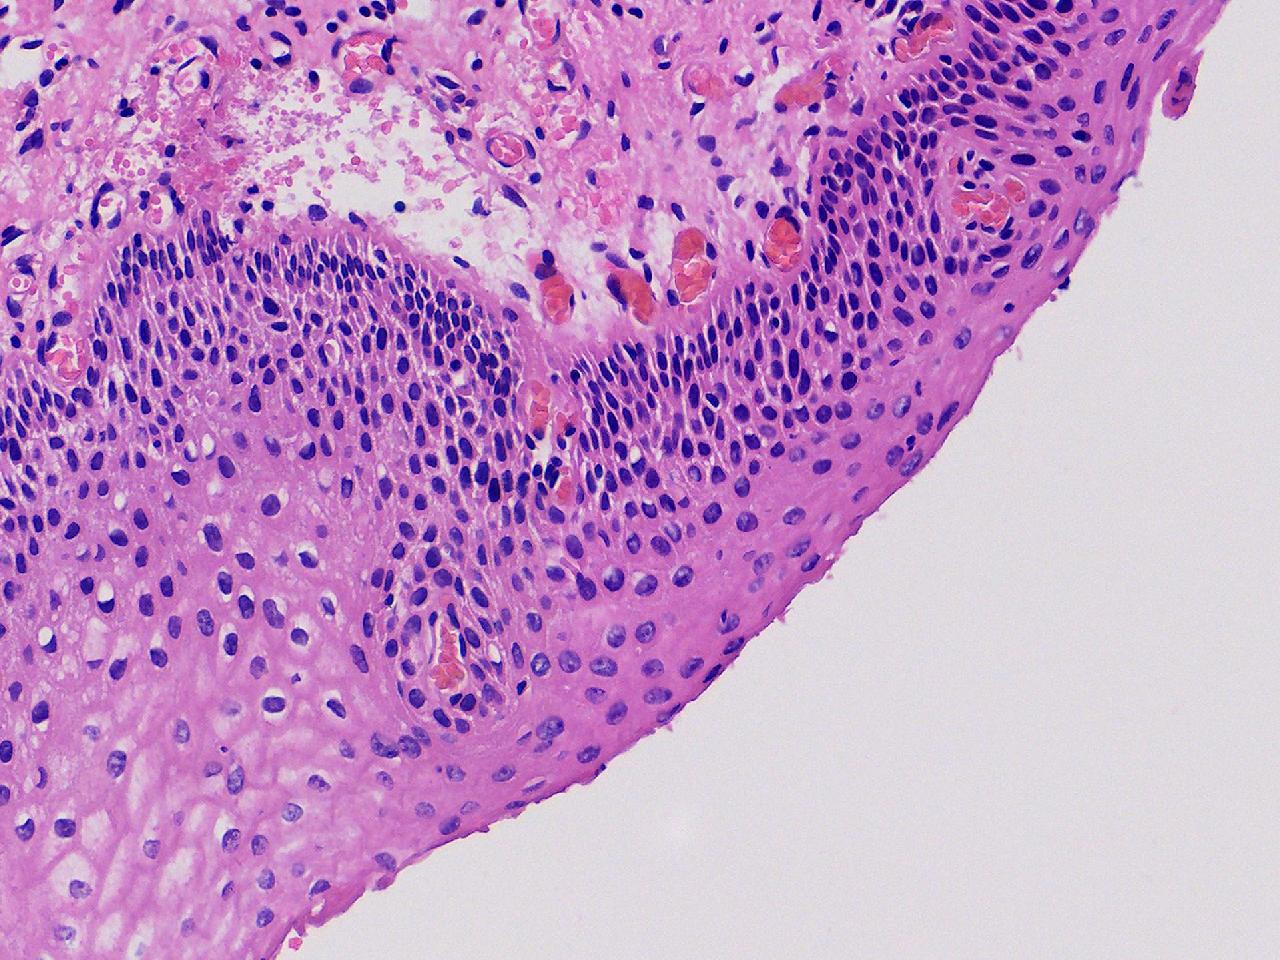

CIN1级? CIN2级?

性别年龄61岁临床诊断

一般病史女,61岁,宫颈活检,,HPV6+ 52+

标本名称宫颈活检

大体所见灰白色不整形软组织1块,直径0.3厘米。

CIN2倒是不够,图3有几个像挖空细胞,HPV有阳,勉强可以考虑小灶LSIL。

• zhuang xia nan:  是的。  2级肯定不够,有挖空细胞,小灶1级。    谢谢老师指点。

CIN1.